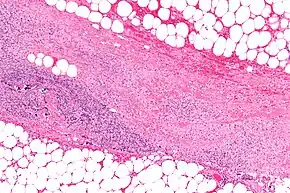

Diagnosis

Early diagnosis is difficult, as the disease often looks early on like a simple superficial skin infection.[4] While a number of laboratory and imaging modalities can raise the suspicion for necrotizing fasciitis, none can rule it out.[17] The gold standard for diagnosis is a surgical exploration in a setting of high suspicion. When in doubt, a small incision can be made into the affected tissue, and if a finger easily separates the tissue along the fascial plane, the diagnosis is confirmed and an extensive debridement should be performed.[2]